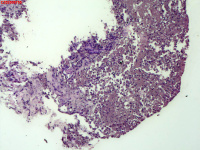

- 右侧胸壁穿刺组织活检

| 性别 | 女 | 年龄 | 81岁 | 临床诊断 | 胸锁关节结核? |

| 一般病史 | 胸部CT示:右肺下叶小结节,建议3-6个月复查,必要时胸外科会诊。左肺上叶多发小斑点、结节影,结核可能。右肺上叶多发点状影。双肺间质性改变。纵隔淋巴结肿大、钙化。右侧胸锁关节见骨质破坏,周围见软组织肿胀。 | ||||

| 标本名称 | 右侧胸壁穿刺组织活检 | ||||

| 大体所见 | B超:体表包块彩超示右侧胸壁混合回声包块,右侧胸壁低回声区,CDFI示:其内未见明显血流信号。 | ||||